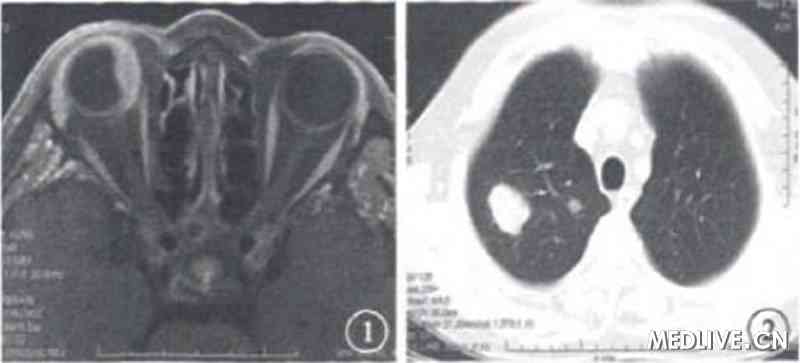

患者女,57岁。因右眼红20d,于外院眼底检查发现右眼鼻上方视网膜黄白色实性隆起;核磁共振成像(MRI)检查,右眼鼻侧占位性病变(图1);CT检查,肺内多个高密度结节状病灶(图2),考虑转移癌于2008年6月6日转诊至我院。

图1 右眼MRI检查像。鼻侧占位性病灶 图2肺部CT检查像。肺内多个高密度结节状病灶

图1 右眼MRI检查像。鼻侧占位性病灶

图2肺部CT检查像。肺内多个高密度结节状病灶